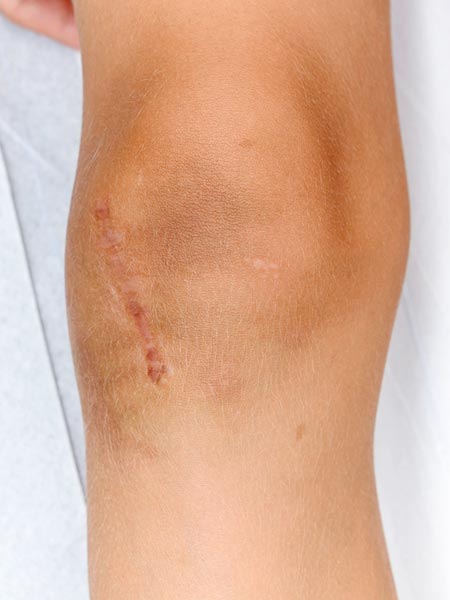

Photograph of the boy, then 7 years old, with slowly progressive, clearly painful swelling laterally at the level of the right knee joint. A distinct pulsation is felt on palpation. Genetically confirmed PTEN hamartoma syndrome.

Photograph of patient 3 months after successful resection of completely embolized PTEN hamartoma.